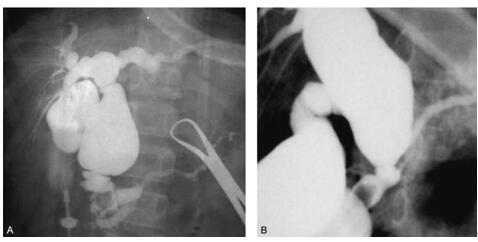

1975年日本学者户谷(Todani)在Alonso-lej分类的基础上增加了第Ⅳ型和第Ⅴ型,即多发性扩张型,肝外胆管扩张同时合并有肝内胆管的扩张及先天性的肝内胆管的扩张。

Ⅰ型,有三个亚型:Ⅰa型,胆总管囊性扩张,常见类型。Ⅱb型,节段性的胆总管囊性扩张,无胰胆合流异常,极少见。Ⅰc型,胆总管梭状扩张,常见类型。

Ⅱ型,胆总管憩室型。

Ⅲ型,胆总管末端囊肿脱垂。

Ⅳ型,是指多发性的肝内或肝外的胆管扩张,分两个亚型。Ⅳa :肝外胆总管扩张同时合并肝内胆管扩张。Ⅳb:肝外胆管的多发性扩张。

Ⅴ型,肝内胆管扩张。但随着对肝内胆管扩张了解的深入,目前多数作者认为这是一独立的病症(Caroli病)。其与先天性胆管扩张症有着本质的区别。详见先天性肝内胆管扩张症。

图6:先天性胆管扩张症的Todani分型

(1)Ⅰa型,胆总管囊性扩张,常见类型。 (2)Ⅱb型,节段性的胆总管囊性扩张

(3)Ⅰc型,胆总管梭状扩张,常见类型。 (4)Ⅱ型,胆总管憩室型。

(5)Ⅲ型,胆总管末端囊肿脱垂。 (6)Ⅳa :肝外胆总管扩张同时合并肝内胆管扩张。

(7)Ⅳb:肝外胆管的多发性扩张。 (8)Ⅴ型,肝内胆管扩张。